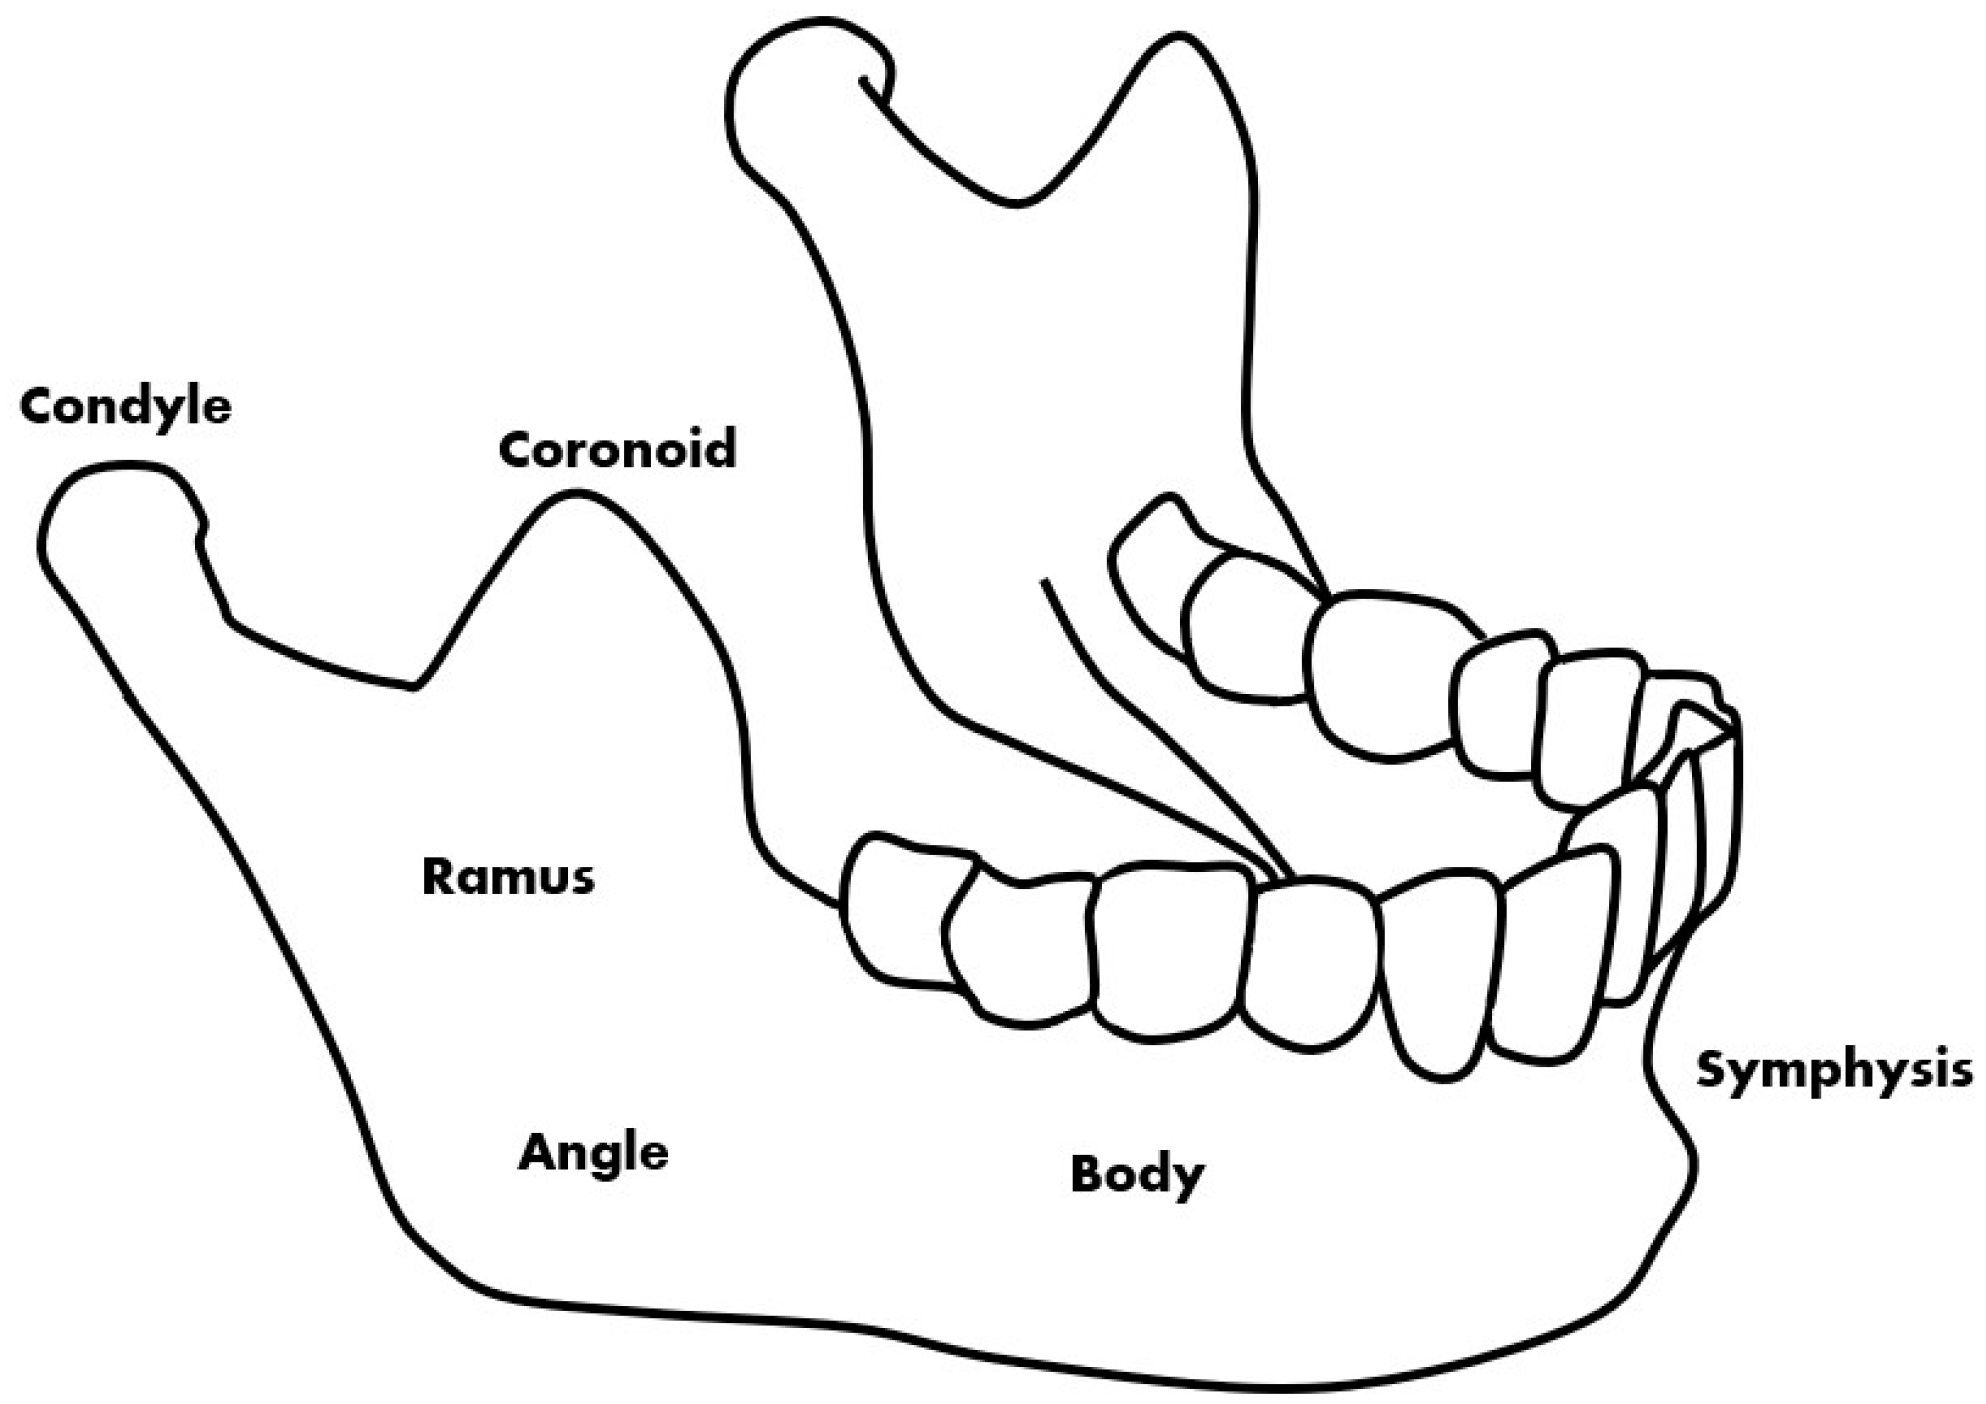

Mandibular fractures are a type of fracture treated in dentistry that are commonly caused by accidents [1]. Patient opinion, panoramic radiographic images, and CBCT (cone-beam computed tomography) images are used for the diagnosis of fractures. Panoramic radiography and CBCT are mainly used to confirm the exact size and location of the fracture during the diagnosis of the patient’s painful area [2]. Fracture locations that are difficult to identify in a panoramic radiographic image are identified through a CBCT image. Deep learning methods using CT are also being studied and it can be confirmed that they have high accuracy [3]. However, because CBCT takes a long time to perform and is more expensive than panoramic radiographs [4,5], this study introduces image deep learning technology to help determine the location of fractures from panoramic radiographic images. This helps the doctor to make a visual diagnosis and can assist in the identification while conserving time and cost. On panoramic radiographic images, the fracture site can be divided into six parts based on anatomical standards [6]. The fracture site is divided into the symphysis, body, angle, ramus, condyle, and coronoid, the most common of which are the symphysis, body, and angle (Figure 1) [1].

Figure 1.

The types of mandibular fractures by region.